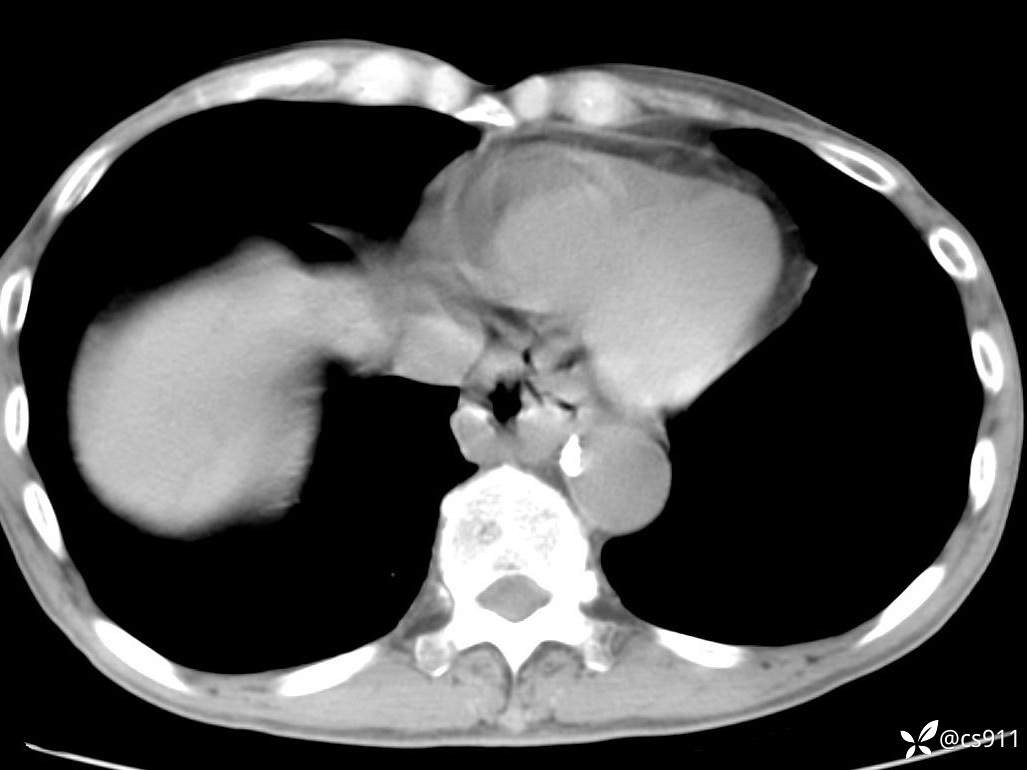

急腹症之急诊CT,原因?答案公布

男,77岁,腹痛、腹胀伴恶心呕吐1天。呕吐胃内容物,非喷射性呕吐,有咖啡色样胃内容物,诉有胃穿孔病史。查体:全腹平,下腹部压痛,全腹无反跳痛,叩诊呈浊音,移动性浊音阴性,肠鸣音减弱,1-2次/分。肛检:直肠未扪及明显肿物,可触及大量粪块。

血淀粉酶(AMY) HH 1859 U/L 35-135

癌胚抗原(CEA) H 27.44 ng/ml 0-5